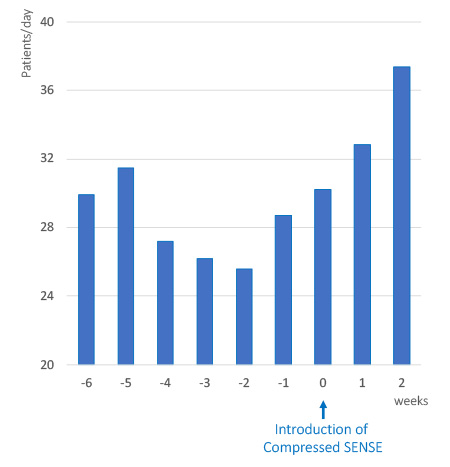

More patients per day

Add extra patient slots to your daily MRI schedule

By using Compressed SENSE on many existing MRI scan sequences, many hospitals have shortened their MRI scan times without sacrificing image quality. A number of hospitals with a high volume of patients have chosen to use these time savings to add extra patient slots to their daily MRI scanning schedule. This has the potential to help hospitals reduce waiting lists and offer a faster MRI service to patients and referring physicians.

More patients per day within the same scanning hours.

Dres. med. Dirk Wagner, Björn W. Raab and colleagues in the Radiology and Nuclear Medicine Joint Practice Göttingen, Germany reported that they shortened exam time from about 15 minutes to 11 minutes on average per patient after implementing Compressed SENSE. This subsequently allowed them to scan 5 more MRI patients per day within the same scanning hours.2